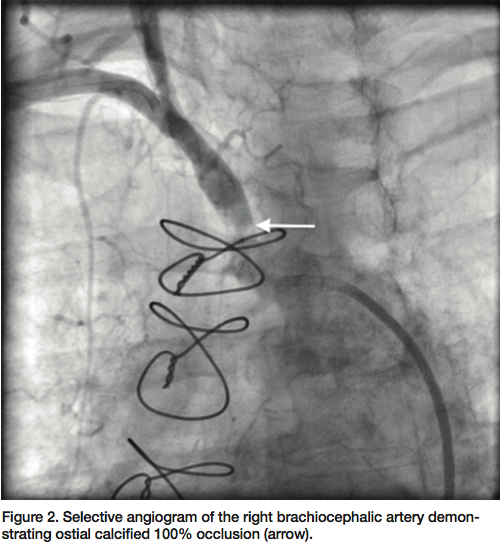

Access was secured in the right brachial artery and right common femoral artery with 6 French

(Fr) and 7 Fr sheaths, respectively. A V-18 wire (Boston Scientific) was advanced with support of a Sterling 4 x 20 mm balloon (Boston Scientific) to cross the right brachiocephalic artery occlusion into the aorta. Selective angiogram through the balloon into the aorta confirmed an intraluminal position in the aortic arch. After serial dilatations, an iCAST (Atrium) 7 x 22 mm covered stent was deployed at the ostium of the right brachiocephalic artery at 14 atm, with good expansion. Final angiogram after post-dilation confirmed brisk flow through the stented segment (Figure 3). Subsequent angiogram of the LIMA graft revealed brisk